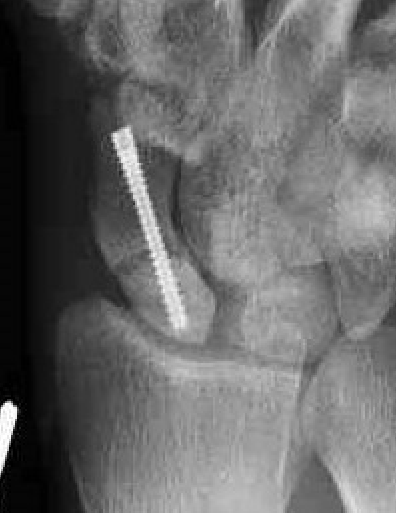

Xray

Increased sclerosis proximal pole post surgery